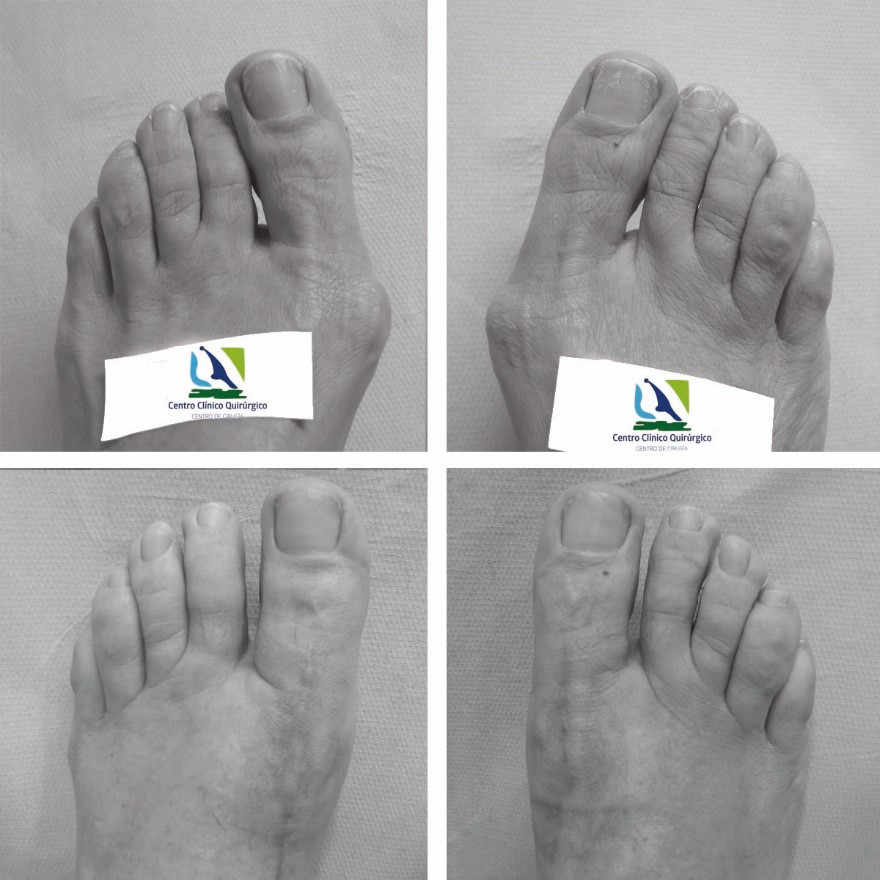

El tratamiento quirúrgico del hallux valgus o juanete será de elección cuando el dolor impida una vida normal y el tratamiento conservador no haya sido eficaz. El objetivo del tratamiento quirúrgico será la eliminación del crecimiento excesivo del hueso y la realineación de los segmentos óseos desviados, así como la corrección de las deformidades asociadas.

Existen diferentes técnicas para la corrección de los juanetes y es el cirujano el que tiene que decidir cuál es la técnica adecuada para cada paciente, ya sea con técnicas de Cirugía Mínimamente Invasiva o por técnicas con incisiones un poco mayores.

El paciente regresa a su domicilio al finalizar la intervención y acudirá a revisiones semanales hasta el alta definitiva que oscilará entre 4 y 8 semanas en función del paciente, el grado de deformidad y la evolución postquirúrgica.

Durante las dos primeras semanas llevará una zapatilla quirúrgica, pudiendo realizar una actividad moderada y las dos semanas siguientes con zapatilla deportiva o similar, posteriormente podrá utilizar su zapato habitual.

Lo más significativo de estas técnicas, es que el paciente está andando desde el primer día de la intervención de juanetes.